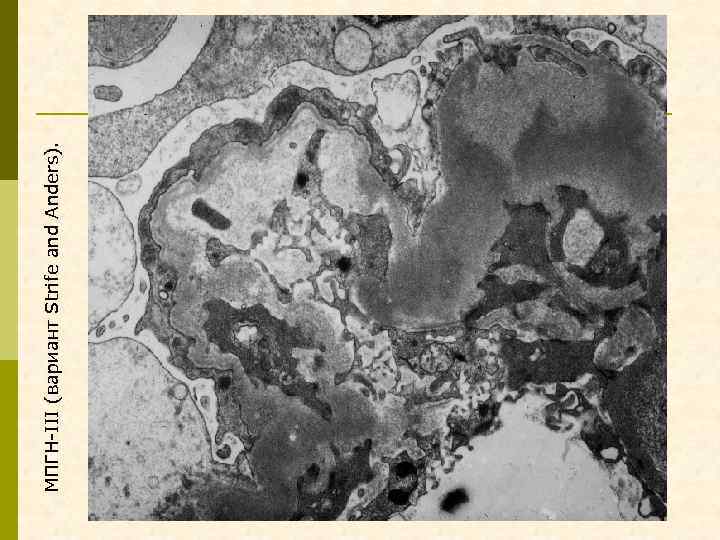

ВАРИАНТЫ ПЕРВИЧНОГО МЕМБРАНО-ПРОЛИФЕРАТИВНОГО ГЛОМЕРУЛОНЕФРИТА МПГН I типа МПГН II типа (DDD) (болезнь плотных депозитов с парциальной дистрофией) МПГН III типа (вариант Strife и Anders, вариант Burkholder)

Эритроцит МПГН, III тип. Грубые изменения ГБМ, резкое утолщение, лакуны, истончение плотной пластины, субэпителиальные депозиты

Гистологические варианты МПГН q Тип I – хроническая иммунокомплексная болезнь q иммунные депозиты в мезангии и субэндотелии q ассоциируется с гепатитом С, смешанной криоглобулинемией, гепатитом В, бактериальным эндокардитом q Тип II – болезнь плотных депозитов q С 3 при иммунофлуоресценции, но без иммуноглобулинов q аутоантитела к С 3 конвертирующему ферменту (C 3 Nef) q в 90% случаев рецидивирует в трансплантате q Тип III – хроническая иммунокомплексная болезнь q в отличие от I типа имеются субэпителиальные депозиты и разрушение базальной мембраны с прозрачными лакунами

МПГН-III (вариант Strife and Anders).